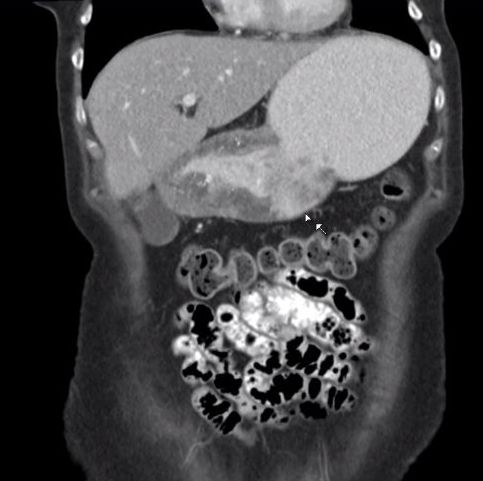

| AEG III | 72-jähriger Mann mit AEG III ypT2 ypN2(5/25) Mo. Intestinaler Bautyp.![]() | |||